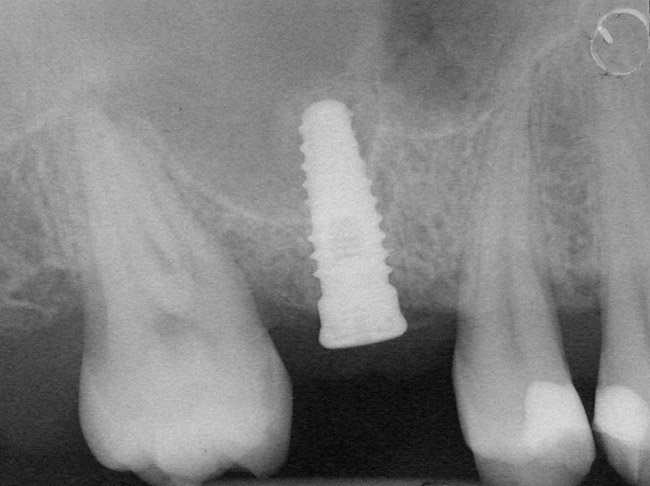

A 53-year-old female was referred for evaluation of a fracture of tooth No. 24. The tooth had been treated endodontically 5 years prior. The radiograph revealed a complete fracture of the tooth involving the crown (Figure 12). Tooth extraction and immediate placement of a an implant that was 10 mm in length and 3.75 in diameter was planned.

At the time of surgery, the tooth was extracted without harvesting any mucosal flap because the implant site was prepared by means of a pilot drill bur (Figure 13) and alternating osteotomes (Figure 14A and Figure 14B). The implant was positioned and showed primary stability. The implant was loaded 2 days after surgery. Then, splinted PFM crowns supported by custom gold abutments were delivered. At 6 months posttreatment, the radiograph revealed no bone resorption and the clinical result was optimal (Figure 15A and Figure 15B).

Figure 12 Preoperative radiograph shows fractured tooth No. 24.

Figure 15B Posttreatment radiograph, 6 months after the initial surgery.

Figure 15  Posttreatment radiograph, 6 months after the initial surgery.

Figure 15b